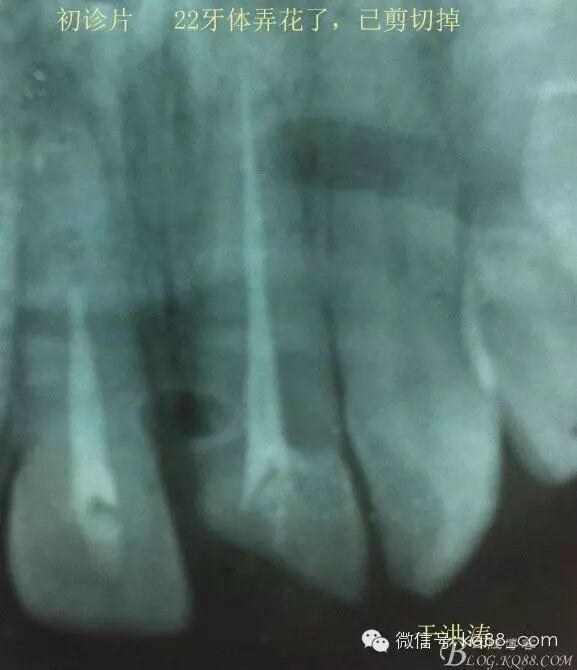

檢查:明顯可見22牙冠橫向斷裂至頸1/3處,近遠中與腭側斷裂至齦下??梢?/span>11牙冠斜向近中斷裂,近中與腭側均斷裂至齦下。21牙冠中1/3有裂痕。11 21 22松動(0),11 21叩(+),22叩(-),11 21 22探(-),11 21 22冷熱(-)。11 21 22唇側牙齦與粘膜和根尖相應部位未見明顯改變。11 22腭側牙齦增生性改變。11 21 22腭側粘膜和根尖相應部位未見改變。11 21 22舌側窩均有充填物。面部左右對稱無改變。余牙正常。(11,21,22牙冠顏色無改變)。 輔助檢查:X線片檢查11 22牙冠均有缺失。11 21 22 髓腔內均有充填物,11充填不到位, 21充填不實,22充填到位髓腔高密度影像。11 21 牙周膜有增寬,21根尖區(qū)有2mm左右低密度影像。未發(fā)現(xiàn)有牙根側穿或斷裂異物。 診斷:11,21慢性尖周炎,11,22殘冠。 治療計劃: 22無需治療。11 21 建議牙齒根管再治療。告知情況及費用。 1,11 21去除根充物。 2,11 21根管治療。 3,11 22纖維樁樹脂核修復。 4,高頻電刀去除11 22腭側牙齦組織到斷面。 5,11,21,22全瓷單冠修復牙齒。 治療過程:經(jīng)患者同意。H銼去除11 21原有充填物,未發(fā)現(xiàn)明顯滲出物,無異味。K銼疏通根管,VDW根測儀測量長度,11牙20mmWL,21牙20mmWL。S3鎳鈦器械預備根管。(全程1%次氯酸鈉沖洗EDTA溶解潤滑)試尖片顯示牙膠未到位,繼續(xù)向牙根尖各2mm進入預備。吸潮紙尖吸干根管,登士柏樹脂根充糊劑輸送至根尖部位,以測量數(shù)據(jù)用牙膠尖冷充側壓充填根管,3M玻璃離子封閉根管口。不可用患牙啃咬硬物,擇日冠修復。 輔助檢查:插針X線片顯示根管內充填物已經(jīng)取出。試尖片顯示牙膠尖未到位,繼續(xù)用K銼和機括向根尖預備。根充結束片顯示根充密實,無超充,無欠充。 醫(yī)囑:常規(guī)醫(yī)囑,不適隨診。 各步驟操作見下圖 于洪濤 2015.02.03 復 診 主訴:無疼痛,不適癥狀已經(jīng)消失。 檢查:11 21 充填物存在邊緣封閉完好,叩(-)松動(0)牙齦及周圍同初診。11 21 22無任何不適。 治療過程:由于患者自身原因即將兩個月來復診。拍X線片,去除11 22髓腔內部分牙膠,P鉆預備根管到達預定位置。粘結纖維樁,制作冠核。初預備11 21 22牙冠。高頻電刀按廠家要求功率和方法去除11 22腭側牙齦組織到達牙齒斷裂部位,調整檔位和功率繼續(xù)凝固和精修腭側組織,11 21 22排齦精修拋光。硅橡膠兩次法取模,可見模型完整肩臺清晰。制作臨時冠,科爾不含丁香油臨時冠粘結系統(tǒng)粘接。 模型送技師制作。預約義齒佩戴時間。(需術前牙齒比色) 輔助檢查:X線片顯示根尖低密度影像消失,牙周未見異常。X線片顯示纖維樁密合到位。 醫(yī)囑:不可用臨時牙肯咬硬物,不適隨診。 各步驟操作見下圖 于洪濤 2015.03.26 復 診 主訴:牙齒無癥狀,自感腭側術區(qū)舌舔粘膜不適。 檢查:臨時冠完整,無松動,邊緣緊密。牙齒無疼痛,唇側牙齦無明顯紅腫,腭側牙齦愈合良好,牙冠肩臺邊緣清晰。腭側牙齦術區(qū)中度觸及有少量滲血。 治療過程:義齒制作完成。去除臨時冠及粘結物。義齒試戴調整完全就位,無懸突,無縫隙。清洗義齒,氫氟酸處理義齒50秒(加強醫(yī)患防護),沖洗吹干,偶聯(lián)劑處理備用。基牙37%酸處理15秒,沖洗吹干,隔濕,排齦,涂第五代粘結劑。小蜜蜂雙固化樹脂水門汀激活攪拌注入義齒中,按順序就位,加壓力,牙線去除牙縫隙多余樹脂,涂阻氧劑,基牙唇腭側各光照固化3秒之后去除多余水門汀取出排齦線,繼續(xù)光照固化牙齒每個面20秒。精細查找去除多余水門汀。 醫(yī)囑:1,患牙咀嚼硬物加以注意。 2,常規(guī)醫(yī)囑,不適隨診,。 3,加強口腔衛(wèi)生意識。定期復診檢查。 各步驟操作見下圖 于洪濤 2015.04.07 回訪病例 主訴:咀嚼食物非常自如,無任何不適。 檢查:義齒牙體完整。無松動,無叩痛。唇側牙齦紅潤質韌無萎縮,腭側術區(qū)牙齦愈合良好,無炎癥改變。唇腭側根尖相應部組織無改變。余牙正常。 輔助檢查:X線片顯示牙根及周圍未見異常。未見骨萎縮。牙冠及頸部未見異常。 醫(yī)囑:定期檢查義齒,不適隨診。 各步驟操作見下圖 于洪濤2015.04.28